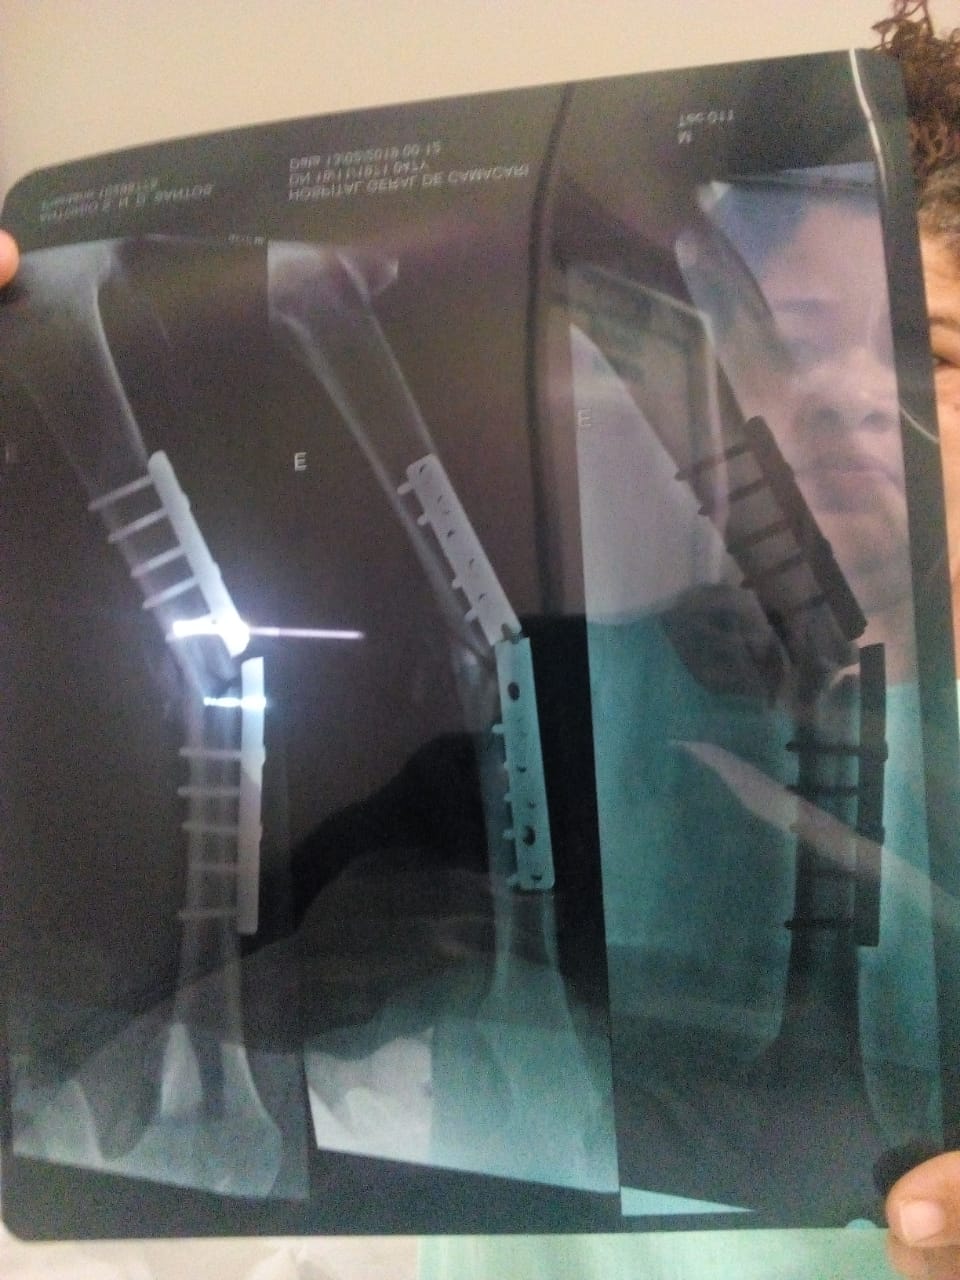

Internado no Hospital Geral de Camaçari (HGC), com fratura no fêmur, depois de sofrer um acidente de moto em novembro último, ter passado por uma cirurgia para implante de uma ‘placa de titânio’ na perna, e ter que retornar ao hospital para substituição da placa, que não resistiu ao seu peso e quebrou, não se sabe se por problema com a colagem do osso ou se por má qualidade do material, o decorador Antônio Sidney Nogueira dos Santos, 47 anos, apelou para o Camaçari Fatos e Fotos (CFF), neste sábado, 16, na esperança de conseguir sensibilizar o Hospital para solução do seu problema.

Muito conhecido na cidade como “Kiko”, o decorador, que é também supervisor no CEMPRE (Centro Médico de Reabilitação Física), órgão médico da prefeitura de Camaçari, e teve a placa rompida em sua perna dois meses depois de implantada, e que afirma que por causa da falta de anestesistas, pacientes estão sendo transferidos para uma cidade da Chapada Diamantina, distante 300 quilômetros do município, e “isso por causa da preocupação do coordenador do Centro Cirúrgico do hospital”, diz que precisa que a classificação da sua cirurgia seja reconsiderada, prometendo acionar juridicamente o Estado em caso contrário. O CFF tentou contato com o hospital, mas não obteve sucesso.